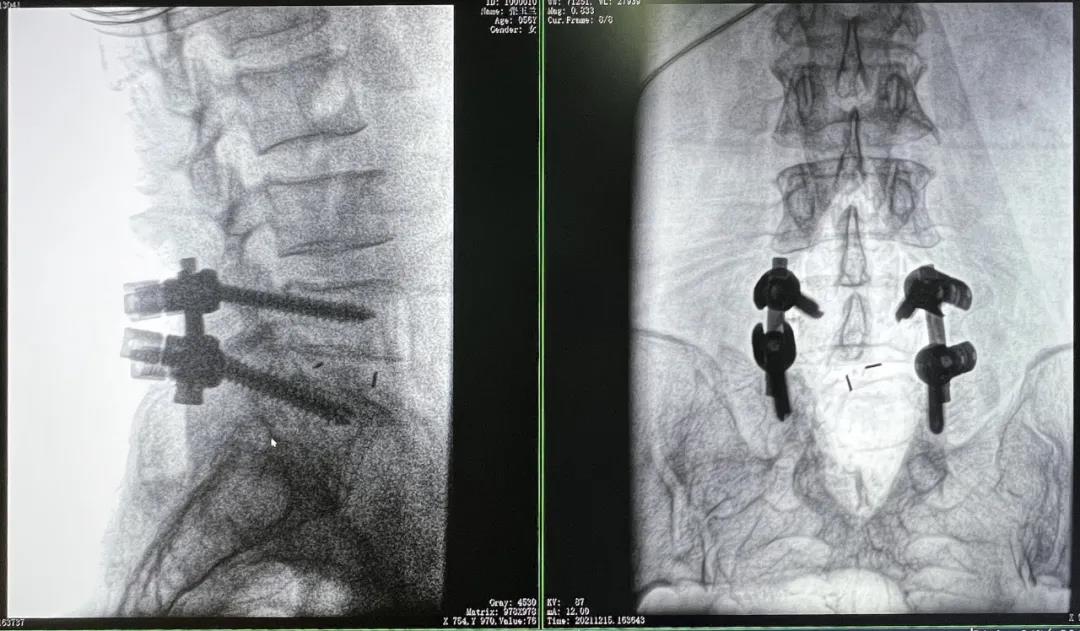

患者1:女性,56歲,L5/S1椎間盤椎板減壓+釘棒固定術(shù)

患者下腰部疼痛,活動受限,伴有左下肢疼痛5年,久站或彎腰干活時疼痛加劇,臥床休息后疼痛癥狀緩解,近一個月情況加重,需行椎板減壓+釘棒固定術(shù)。

3D C形臂擺位及手術(shù)前二維影像

醫(yī)生在影像引導(dǎo)下在L5/S1椎弓根處打入醫(yī)用螺釘